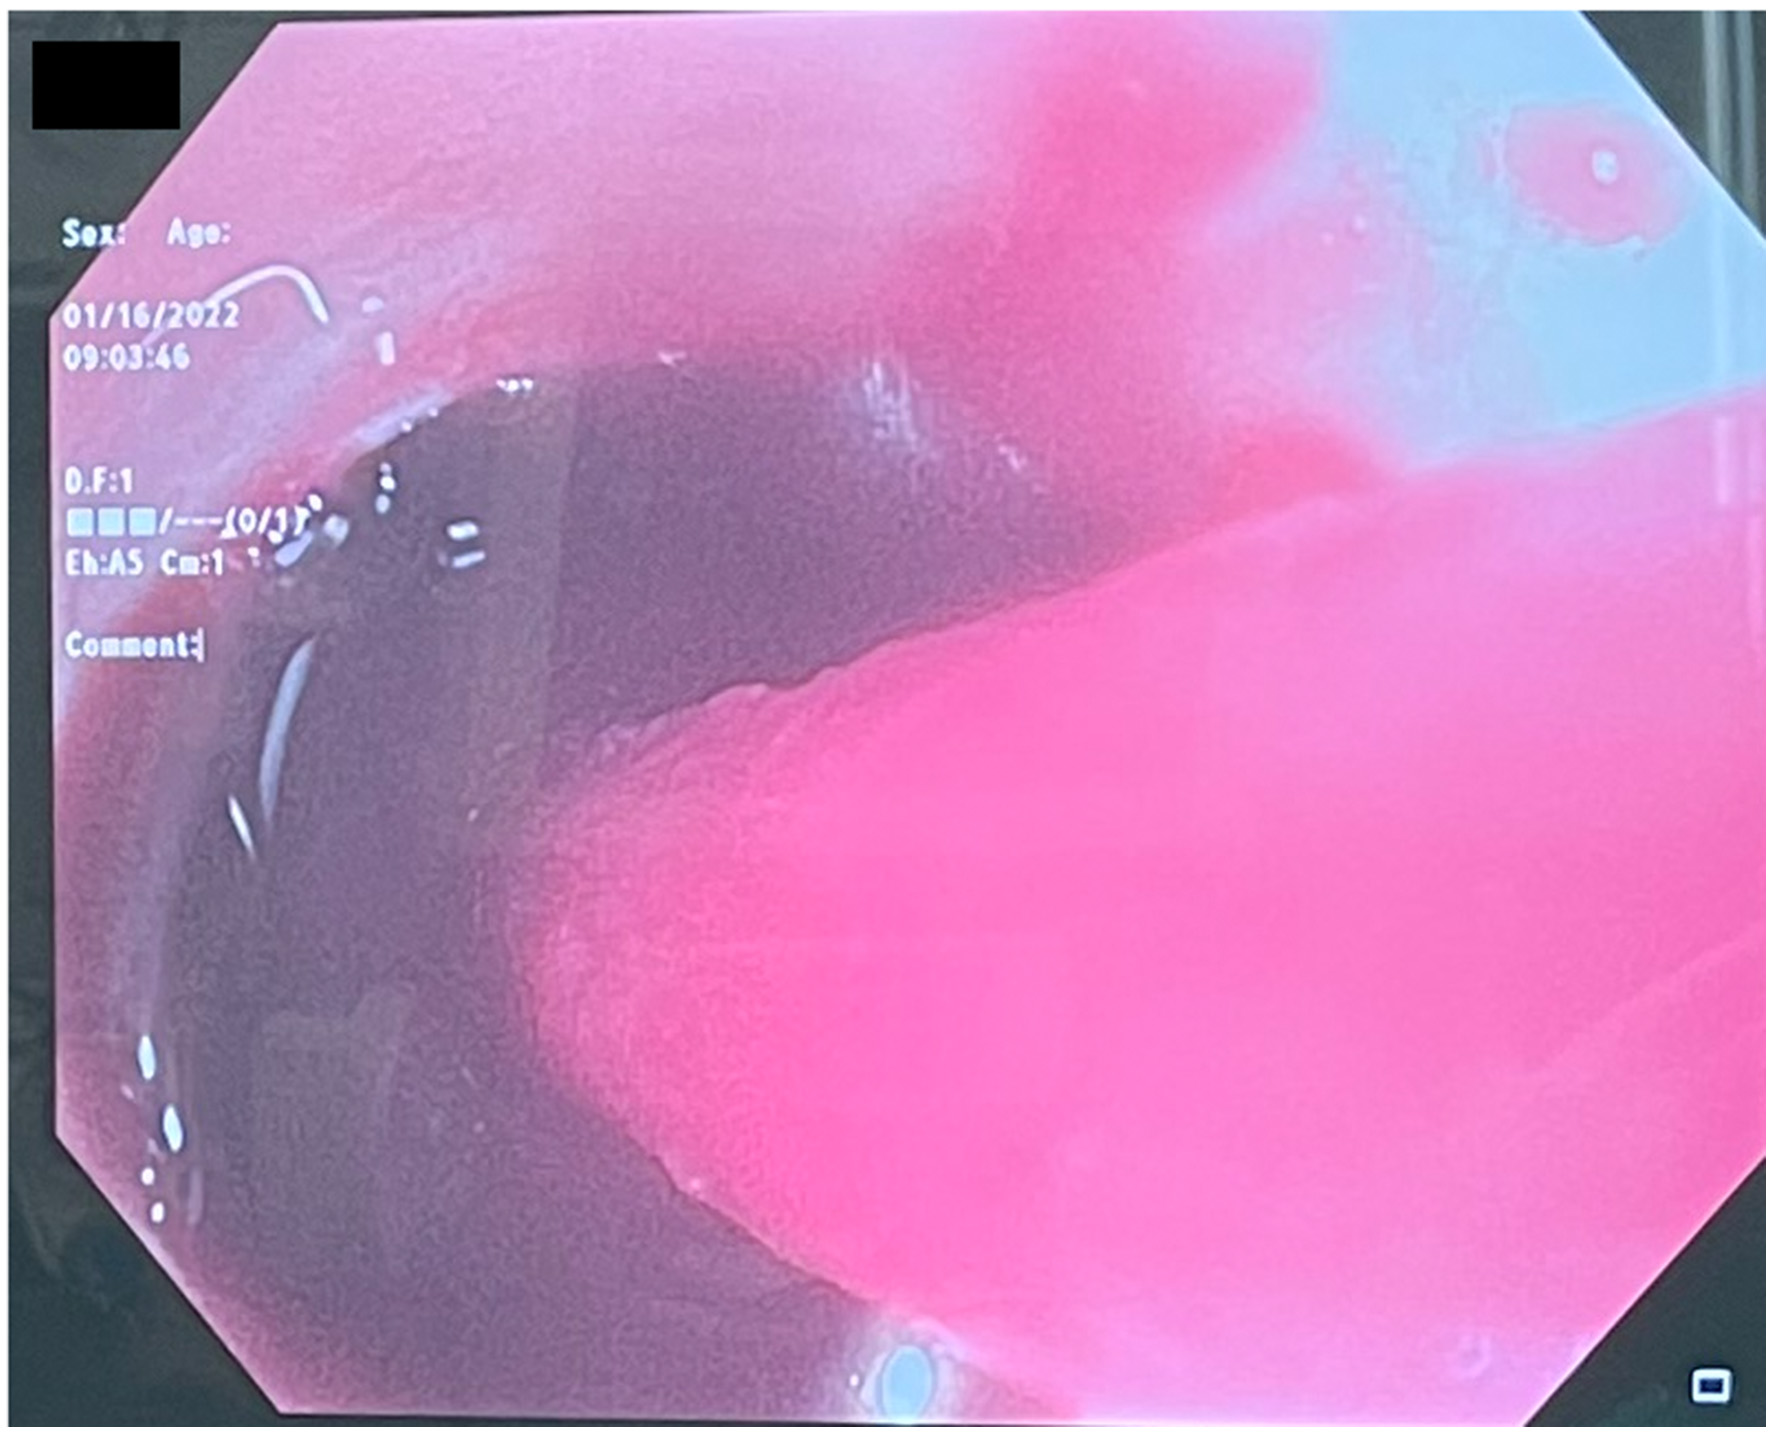

Figure 2

Bronchoscopy reveals massive hemoptysis.

Several days after tracheostomy (hospital day #18, VV ECMO day #11) hemoptysis developed and it persisted despite holding heparin drip and normal platelet counts. His chest x-ray demonstrated bilateral opacifications (Figure 1). Dark blood was suctioned continuously from the tracheostomy and hemoglobin repeatedly dropped requiring transfusions. VV ECMO settings were increased to 100% FiO2 as the VV ECMO sweep was maximized to 11 L/min to maintain SpO2 >85%. Bedside bronchoscopy revealed massive bleeding in the left and right main bronchi. Ice cold saline and epinephrine lavage failed to control the bleeding, thus the site of bleeding was unable to be identified. Despite the evacuation of more than 500 cc of blood under bronchoscopy, there was continued hemorrhage from both main bronchi (Figure 2). The tracheostomy tube was removed to examine the stoma, and no active bleeding was identified in that area. A direct suction was then attempted, inserting a Yankauer suction catheter into the trachea via the tracheostomy stoma (Figure 3). This was also unsuccessful in clearing the airway. In further attempts to control bleeding, continuous bronchoscopy was performed for 4 h with the maintenance of adequate SpO2 >85% despite discontinuation of the ventilator.